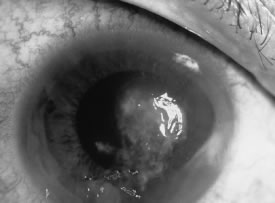

There is no distinguishing clinical sign by which to recognize the genus or species of the infectious filamentous fungus. F. solani is the most virulent organism and typically produces rapidly progressive infection characterized by epithelial and stromal ulceration, dense stromal necrosis, abundant cellular infiltrate, and edema in the adjacent stroma and hypopyon (Figs. 8 and 9). Delicate feathery components are transient. Individual hyphal fragments are rarely visualized. Infection by certain species of Aspergillus and Scedosporium (Figs. 10 and 11) resembles F. solani keratitis and progresses rapidly. Infection by less virulent organisms, such as Curvularia and Alternaria species, produces small, focal (less than 3-mm diameter) areas of nonnecrotizing stromal inflammation with delicate feathery borders (see Fig. 1 and Fig. 12). Macroscopic pigmentation may develop in keratitis caused by Alternaria, Curvularia, and other dematiaceous fungi (Fig. 13).4,11,14 The central component may progress to dense, opaque, gray-white suppuration in the deep stroma without enlargement in total area and may be accompanied by mild inflammation in the adjacent stroma. Iritis is minimal to moderate. Infection caused by other, relatively less virulent organisms resembles herpes simplex or noninfectious keratitis (Fig. 14).

Fig. 10. Scedosporium apiospermum keratitis in a 53-year-old woman, 10 days following unknown foreign body injury while gardening. Epithelial and stromal ulceration, endothelial plaque, and hypopyon. Note the corneal edema surrounding the central area of suppuration.

Fig. 11. Scedosporium apiospermum keratitis. Note the dense, suppurative stromal keratitis and hypopyon.